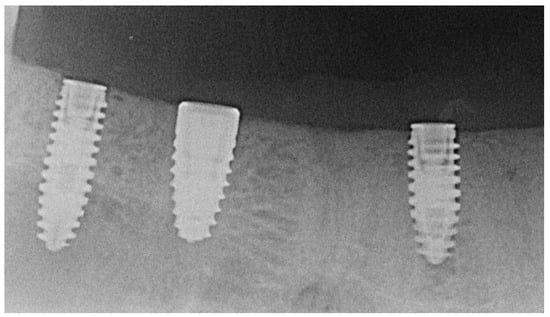

| Control (Straumann BLT®) | 8 | 27.6 | 2.3 | 8 | 0.15 | 0.28 | 6 | 61.5 | 21.4 | 8 | 50.00 | 18.71 | 16 | 2.80 | 1.67 |

| Test Porous (AlfaGate MT®) | 7 | 26.0 | 1.0 | 7 | 0.33 | 0.08 | 6 | 63.8 | 20.8 | 6 | 55.83 | 23.69 | 14 | 2.76 | 2.07 |

| Test Bioactive (AlfaGate MT®) | 9 | 26.5 | 1.1 | 10 | 0.34 | 0.08 | 10 | 76.1 | 8.9 | 9 | 48.11 | 22.89 | 14 | 4.07 | 3.35 |